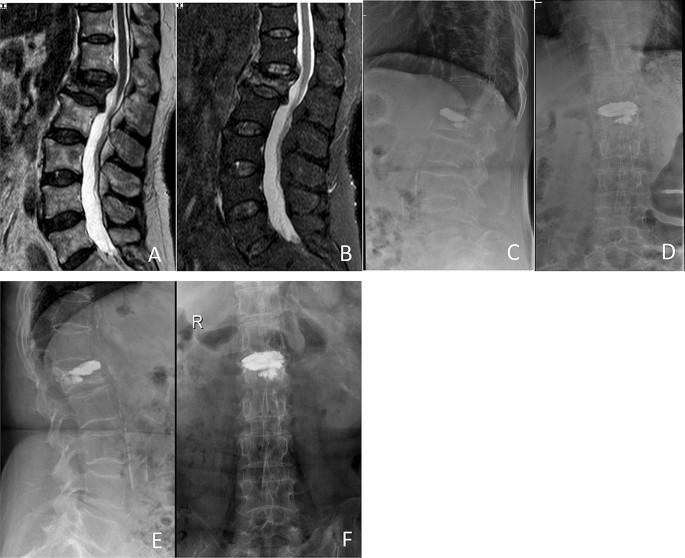

PKP: Balloon tamp was inserted through the previous needle channel and placed in the anterior three quarters of vertebrae body. The balloon was then inflated slowly until it contacted the endplate or the inflation pressure reached 200 psi. Conventional low-viscosity bone cement was manually injected to the cavity with a high pressure pump after removal of the balloon (Fig. 2).

Preoperative and postoperative films of a 60-year-old woman with OVCFs of L1 vertebral body, treated with low-viscosity cement PKP. Preoperative MR image showing the compression fracture at the L1 level (A), (B). Anterior–posterior and lateral film showing the leakage of bone cement into the upper disc space postoperatively (C), (D) and at 1 year postoperatively (E), (F).